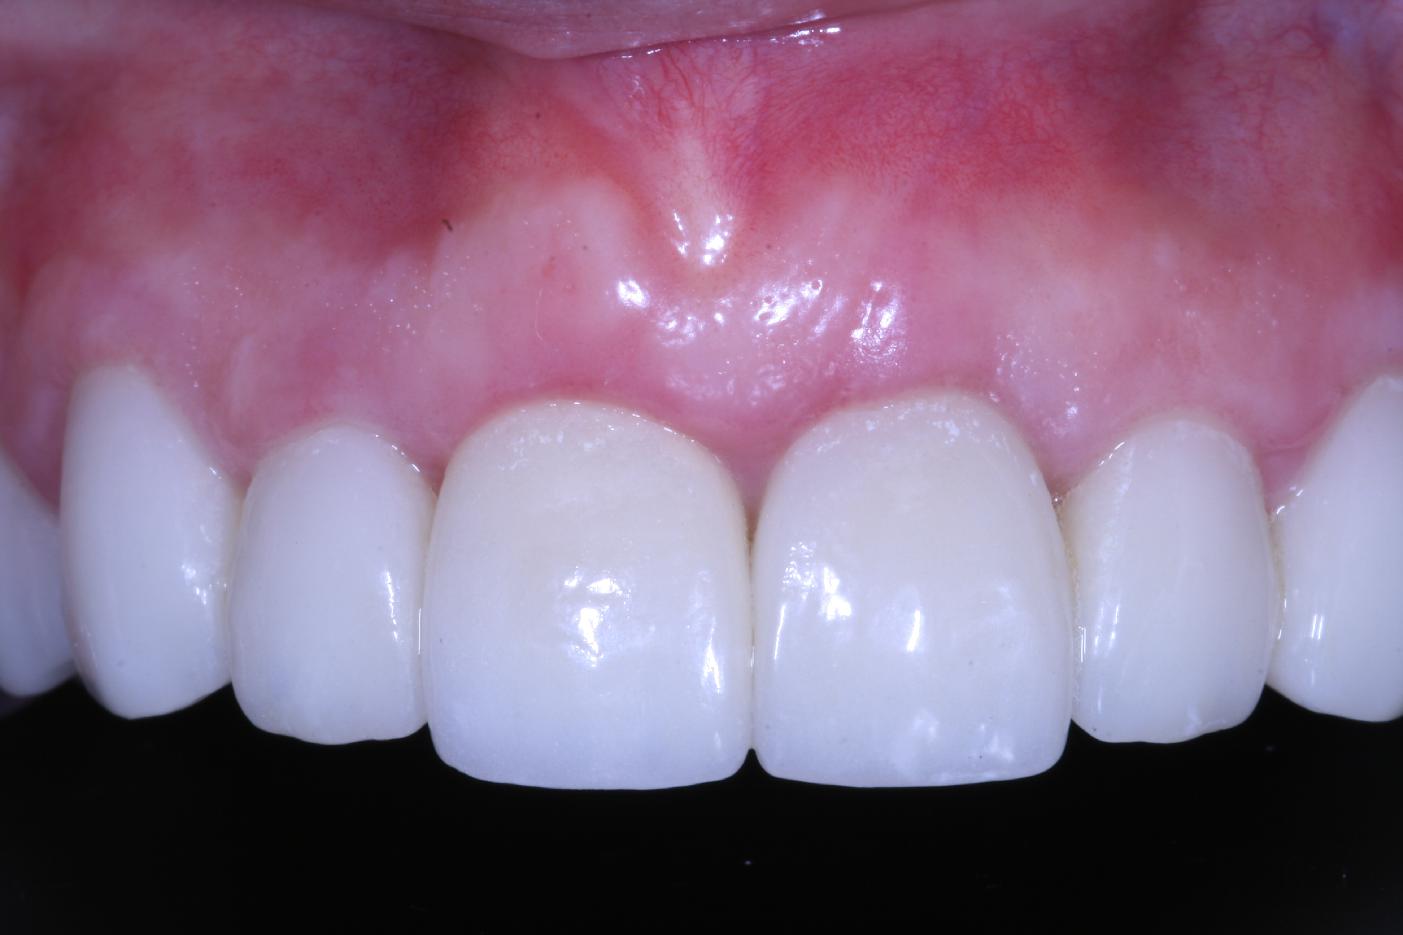

Initial situation - A young female 34 years old lost her front teeth in an surfing accident and she had a 5 unit bridge supported by her upper left lateral and right canine. The restoration failed and both supporting crowns have exposed and leaking margins.